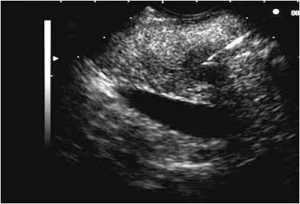

Обратите внимание, поджелудочная железа не относится к полым органам, ее основа — паренхиматозная ткань, поэтому полипы в ней появляются не часто. Тем не менее, все же иногда встречаются и в основном в поджелудочных протоках. Кроме этого, их очень трудно обнаружить, так как для них характерно бессимптомное присутствие, особенно в начале их формирования. Правда, на УЗИ они прекрасно обнаруживаются.

- УЗИ.

С помощью ультразвукового исследования оценивают общее состояние тканей, протоков, выявляют наличие опухолей, кист, рубцов.

Единственное место, где они могут возникать, – это протоки поджелудочной. Но в этом случае они никак себя не проявляют, что значительно затрудняет диагностику. Более того, полипы поджелудочной железы редко обнаруживаются даже при ультразвуковом исследовании, так как они, как правило, имеют маленькие размеры и носят единичный характер.

- УЗИ. С его помощью обнаруживают крупные новообразования, однако этот метод не подходит для диагностики мелких гормонпродуцирующих опухолей.

Выявлением подобной проблемы должен заниматься гастроэнтеролог. Такие доброкачественные образования быстро определяются, когда сопровождаются выраженной симптоматикой. В остальных случаях диагностика во многом затруднена, так как у пациента нет четких жалоб, которые лечащий врач, собирающий анамнез, может учесть и установить характер проблемы. Для определения состояния поджелудочной железы требуется ультразвуковое исследование. Если крупные образования не выявляются, может потребоваться проведение МРТ или КТ.